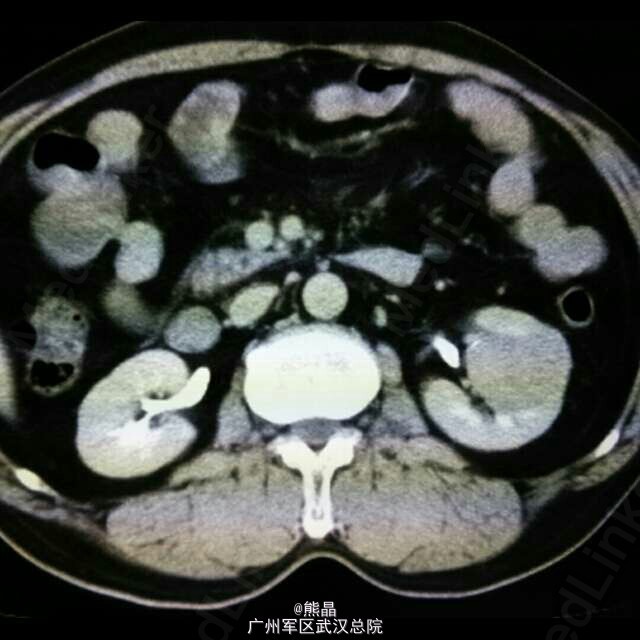

患者男性,61岁,体检发现左肾占位病变5天,无明显临床症状。 肾脏嗜酸性细胞瘤是一种少见的肾脏良性肿瘤,与肾癌鉴别较困难。 肾脏嗜酸性细胞瘤增强扫描可以出现轮辐状强化,是其特征之一,肿瘤中可见星状瘢痕,为纤维母细胞增生,如肿瘤中有钙化,可以除外嗜酸。